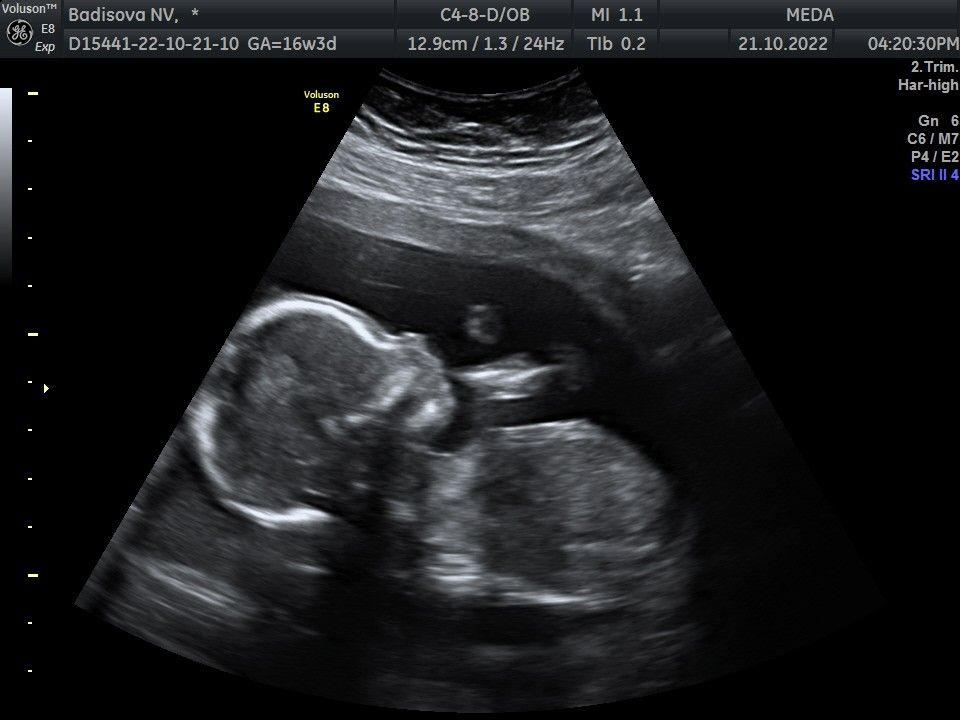

упавшая с метлы, мальчик это круто))) Изображение Во какой красавец))) и прически вязать не надо 🤣🤣

Ли Ра, а у меня пока вот такой красавчик Изображение